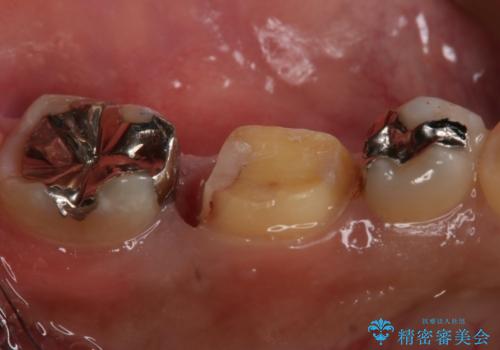

- 左下6番の銀歯が不適であったためやり変えを勧めたところセラミックでの治療を希望された患者様です。

切削量などを考慮し、フルジルコニアクラウンでの治療を選択しました。

う蝕が歯髄に近接していたので麻酔が切れた後に痛みなどの症状が出る可能性をお伝えしています。

う蝕が深く切削量が多くなりましたが痛みなどは起きなかったので、予定通りフルジルコニアクラウンでの治療で進めました。